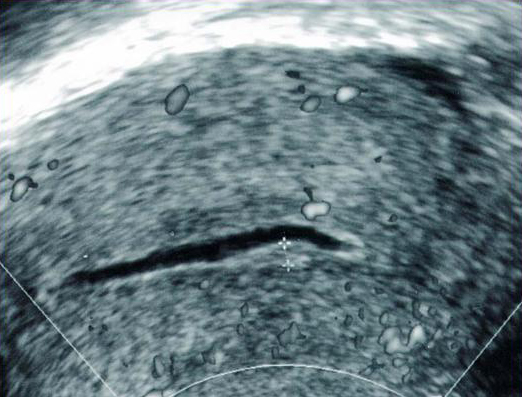

Hyperplasie focale de l’endomètre